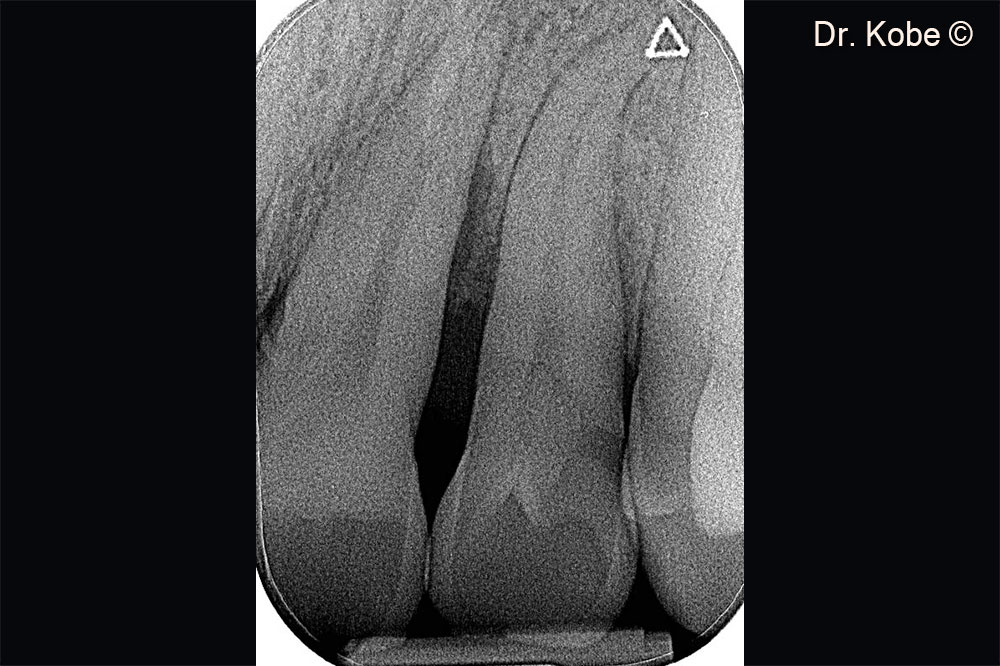

Khuyết tật xương theo chiều dọc trên phim chụp X-Quang